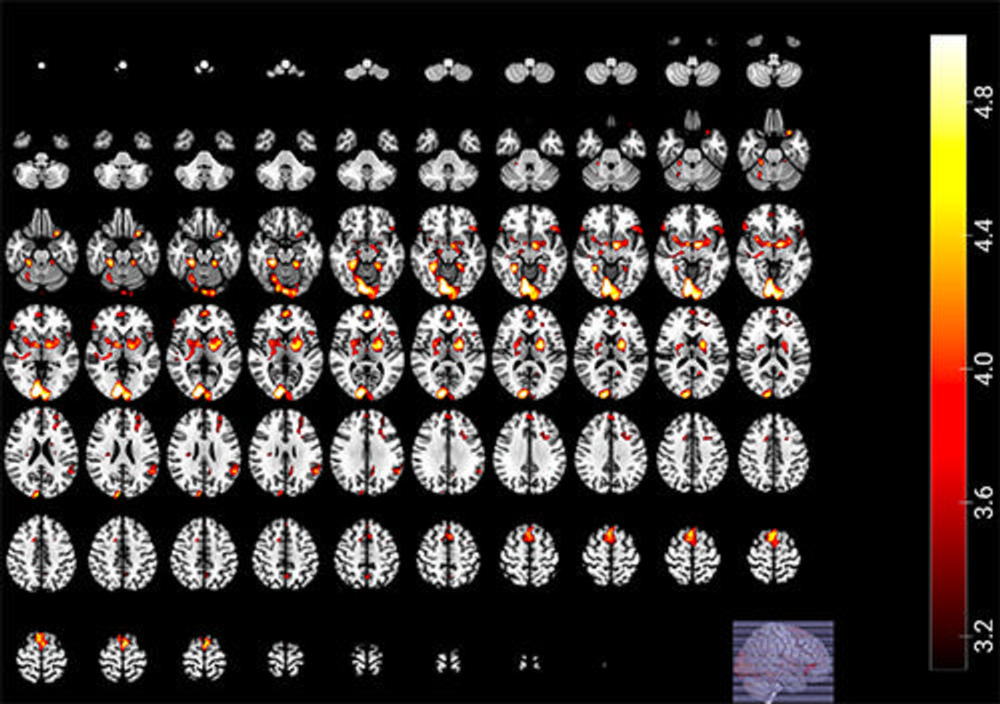

Figure 1. Significant victory contrast shows the result of the subtraction of brain activations of fans when their team scores goals against the archrival minus when they score goals against another (non-relevant) team (Fan->Rival > Fan->Other).

High-res (TIF) version